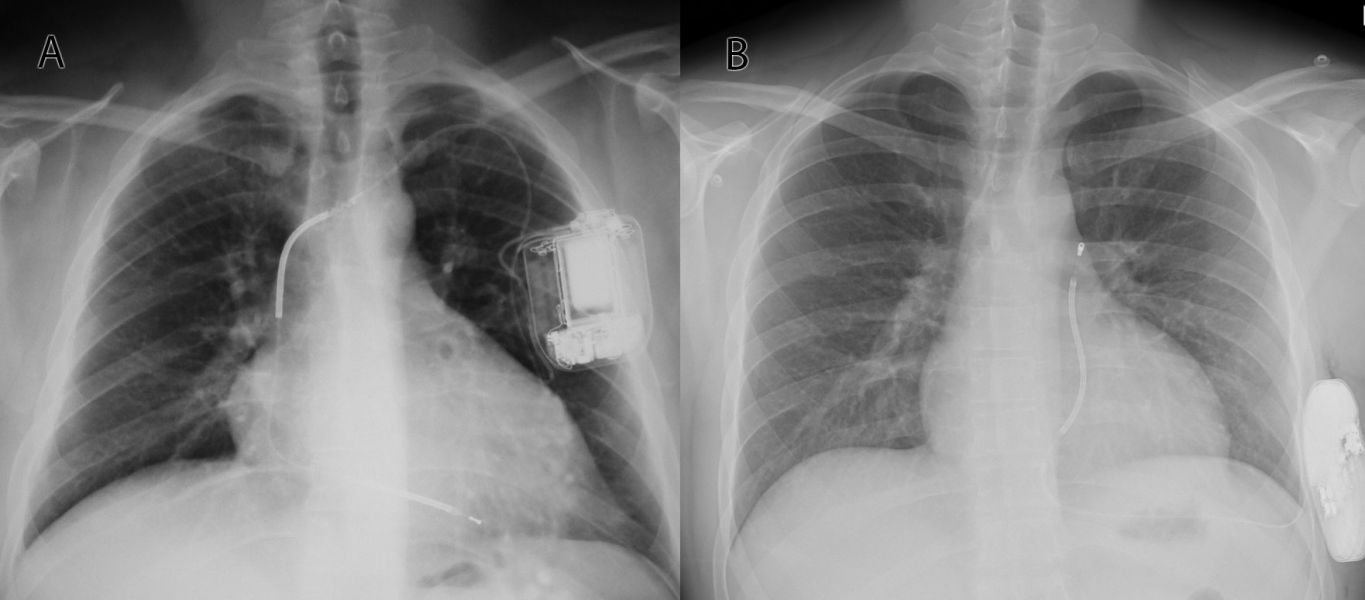

Důležitým faktorem, kterému je v doporučených postupech věnována samostatná kapitola a který má zásadní význam pro snížení počtu intervencí ICD a může mít vliv i na prognózu pacienta, je správná programace detekce a terapie KT.25,26 Parametry programace ICD, které účinně snížily výboje a vedly k poklesu mortality, zahrnovaly prodlouženou dobu detekce, použití diskriminačních algoritmů na rozlišení supraventrikulárních a komorových arytmií, detekci ve více zónách a systematické používání antitachykardické stimulace. Vzácně může být implantace ICD spojena se závažnými komplikacemi. Mezi nejčastější patří poškození integrity elektrody, aplikace neadekvátní terapie a infekce kapsy přístroje. Části komplikací souvisejících s transvenózní elektrodou se netýkají subkutánních ICD (S‑ICD). S‑ICD (obr. 1) nemá intravaskulární elektrodu a nemůže dodat antibradykardickou a antitachykardickou stimulaci. Ve studii PRETORIAN, která srovnávala S‑ICD oproti transvenóznímu ICD, byla prokázána pro S‑ICD non‑inferiorita.27 S‑ICD lze proto použít jako alternativu k transvenóznímu ICD v případě, kdy není potřeba kardiostimulace, antitachykardický pacing či resynchronizační terapie.

Obr. 1 Skiagram s implantabilním kardioverterem‑defibrilátorem (ICD). Panel A ukazuje konvenční ICD s defibrilační elektrodou implantovanou přes žilní řečiště do hrotu pravé komory. Panel B zobrazuje subkutánní ICD, který je implantován do oblasti střední axilární čáry, elektroda je vedena nad žebry a hrudní kostí v podkoží.